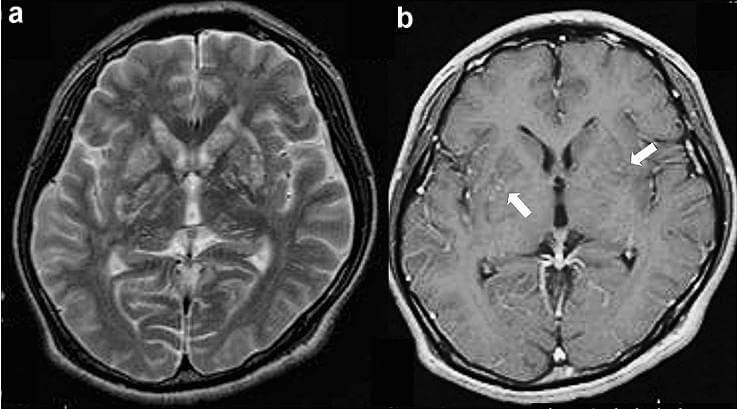

Years later, testing suggested Pistorius had suffered from cryptococcal meningitis, a rare fungal infection that can cause severe brain inflammation. The illness is known to develop slowly and can lead to coma, neurological damage, and long-term disability if untreated. In rare cases, patients survive but are left with profound physical impairment despite preserved cognition.